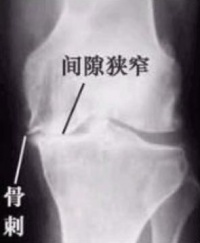

人体的关节活动久了也容易发生病变。骨疣一般好发于活动较频仍的关节,由于这些关节长时间反复使用,因此很容易发生磨损与退化的现象。而身体容易诱发骨刺生长的地方包括颈椎腰椎膝关节、脚跟,另外,手指跟手肘也是骨刺容易发生的部位。

骨疣诊断[编辑 | 编辑源代码]

在颈椎、腰椎形成的骨刺,如果有压迫到神经根或脊髓,才会造成上肢下肢的疼痛和麻痛感,而这些骨刺大多是年老或劳动者其脊椎退化而造成,不过并不是所有 的骨刺都会压迫到神经。上肢或下肢的酸痛麻现象,可以先以药物治疗,或是利用物理治疗,如果症状严重到影响到生活质量,再考虑开刀也不迟。

是脊椎因应退化而自行补强的一种现象,一般来说,如果没有压迫到神经的话,其实不需过分担心,随著年龄增加,每个人或多或少都会有长骨刺的情形,而X光上出现骨刺也不见得就需要接受治疗,只有在骨刺压迫到神经引起其他症状时,才需要进一步接受治疗。